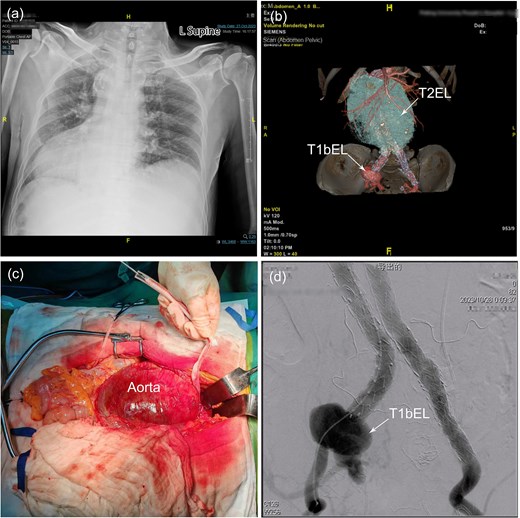

(a) Chest X-ray shows dextrocardia and dilation of the mediastinal shadow. (b) Contrast-enhanced computed tomography demonstrated a previous stent–graft placement, a type II endoleak with a giant aneurysm sac, a distal right common iliac artery dilatation with a type Ib endoleak. (c) Identification of a huge infrarenal aortic aneurysm through a mid-abdominal incision and was subsequently controlled with a sleeve to facilitate subsequent surgical procedures. (d) Angiography revealed a significant type Ib endoleak in the distal to the right common iliac branch. AA, abdominal aorta; CIA, common iliac artery; LRA, left renal artery; RRA, right renal artery; T1bEL, type 1b endoleak.

Following a comprehensive multidisciplinary consultation, a hybrid surgery approach was deemed the most appropriate strategy to address the complex ELs. Due to the patient's congenital anomaly, the patient–surgeon positioning was mirrored compared to a standard laparotomy setup. Under general anesthesia, a transperitoneal approach was utilized to access the giant infrarenal aortic aneurysm through a midline abdominal incision (Fig. 1c). Proximal aortic control was achieved using a nylon strap. Percutaneous access was then established via the Seldinger technique, through which a vascular catheter (DQ06112121S, Beijing Demax Medical Technology Co., Ltd.) was advanced into the femoral system. The catheter was subsequently exchanged for an extra-stiff guidewire (G4535, 0.035-inch, Cook Medical) and a 4F pigtail catheter (PV411038PIG, Merit Medical). Intraoperative angiography (Fig. 1d) confirmed the presence of a T1bEL within the right CIA. The right internal iliac artery (IIA) was patent, while the left IIA was not occluded. To address the T1bEL, a distal extension of the graft was deployed into the right external iliac artery (EIA) using Endurant II Stent Graft Systems (ETLW-16-16-C-93-EE&ETLW-16-16-C-124-EE, Medtronic).